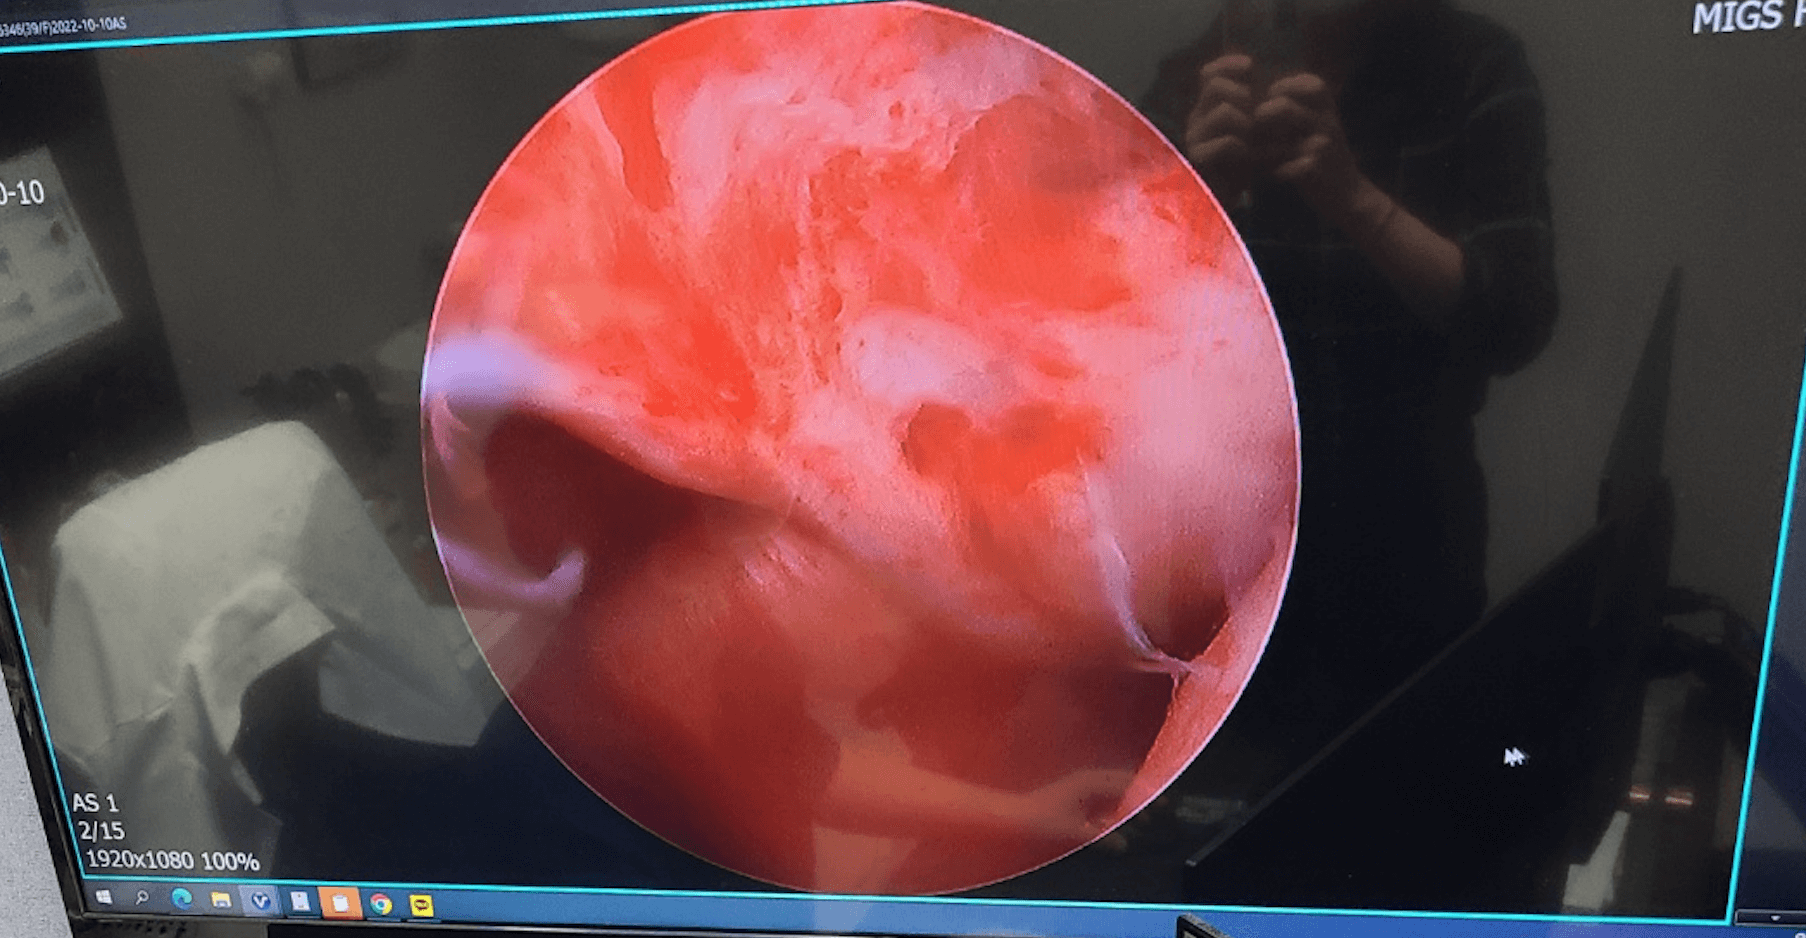

MRI를 찍으니 화면상 50%이상 회전근개가 파열되었다고 의사가 이야기를 했으며, 이런경우 수술하는게 맞다고 하여, 나름 인터넷을 찾아보고 꼭 해야하는지 점검을 했습니다.

즉 회전근개파열을 수술 하면서 어깨에 자라난 뼈를 깍아내는것도 함께 진행 해야 합니다. 그렇게 저는 MRI를 찍고 수술을 진행 하였습니다.

수술을 하고 난뒤 알았다 회전근개파열이 생각보다 많이 되지 않아, 충돌중후군 어깨견봉만 깍고 그안에 콜라겐을 집어 넣었다고 한다. 그래서 의사에게 이렇게 물어보았다.

어짜피 수술 하는김에 회전근개파열된을 같이 하면 안되었냐고, 그리고 시간이 지나면 계속적으로 파열이 된다고 그렇게 들었는데, 여기에 대한 의사의 답변은 MRI상으로는 50%이상 이였는데 막상 열어보니간 그정도는 아니고 염증이 너무 많아서 염증을 제거하는데 오랜시간이 걸렸다.

그리고 이정도면 재활과 같은 치료로 많이 좋아질수 있고, 어깨 회전근개파열된 부분을 지금 묶게 되면 뭐가 좋지 않다고 했는데, 아무튼 시간이 지나면 다시한번 더 해야하나 그런 생각이 들고, 어짜피 자라난 뼈때문에 제거는 해야 했으니 그럴려니 합니다.